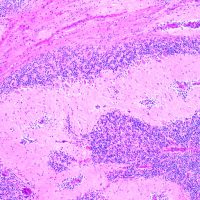

照射後の奇形腫の病理像

左上にはcartilage,右上にはkeratin squamous tissueがみられます。左下は繊維生組織のみdense collagenous tissueです。

生検術で胎児性癌と未熟奇形腫の混合型と診断されたために,化学療法と61.1グレイの放射線治療がなされていました。しかし,大きな松果体腫瘍が残り全摘出したものです。この子の腫瘍は治っていて元気に暮らせています。

奇形腫の照射後はいつもそうなのですが,dense collagenous tissueとfibroblastic spindle cellが組織の主体となっています。要するに肉芽腫のようなものです,ですから,手術摘出ではものすごく硬い線維性の腫瘍となっていてハサミでも切れずに難渋します。出血もしないし脳とは剥離できるのできます。放射線化学療法前の生検による組織像(悪性要素)は消失して単なる成熟奇形腫との病理診断となってしまいます。しかし,この組織のどこかに悪性度の高い細胞が潜んでいて,播種再発するなどということも経験しました。放射線治療後の病理組織診断はその後の予後の予想のためには役に立ちません。